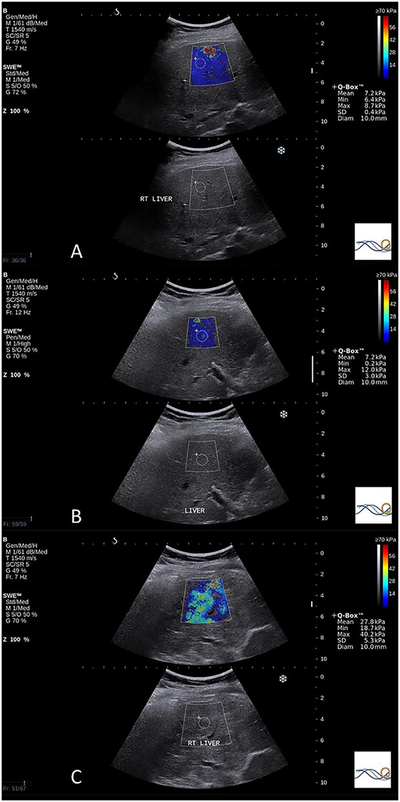

Figure 1.

Examples of the estimated tissue Young modulus obtained from patients with ALD. A, Median estimated tissue Young modulus of 6.85 kPa in a patient with a METAVIR fibrosis grade of F0, necroinflammatory score of 0, steatosis grade of S2, and PBC stage of S0. B, Median estimated tissue Young modulus of 11.30 kPa in a patient with a METAVIR fibrosis grade of F1, necroinflammatory score of 2, steatosis grade of S1, and PBC stage of S0; C, Median estimated tissue Young modulus of 25.75 kPa in this patient with a METAVIR fibrosis grade of F3, necroinflammatory score of 2, steatosis grade of S2, and PBC stage of S3.